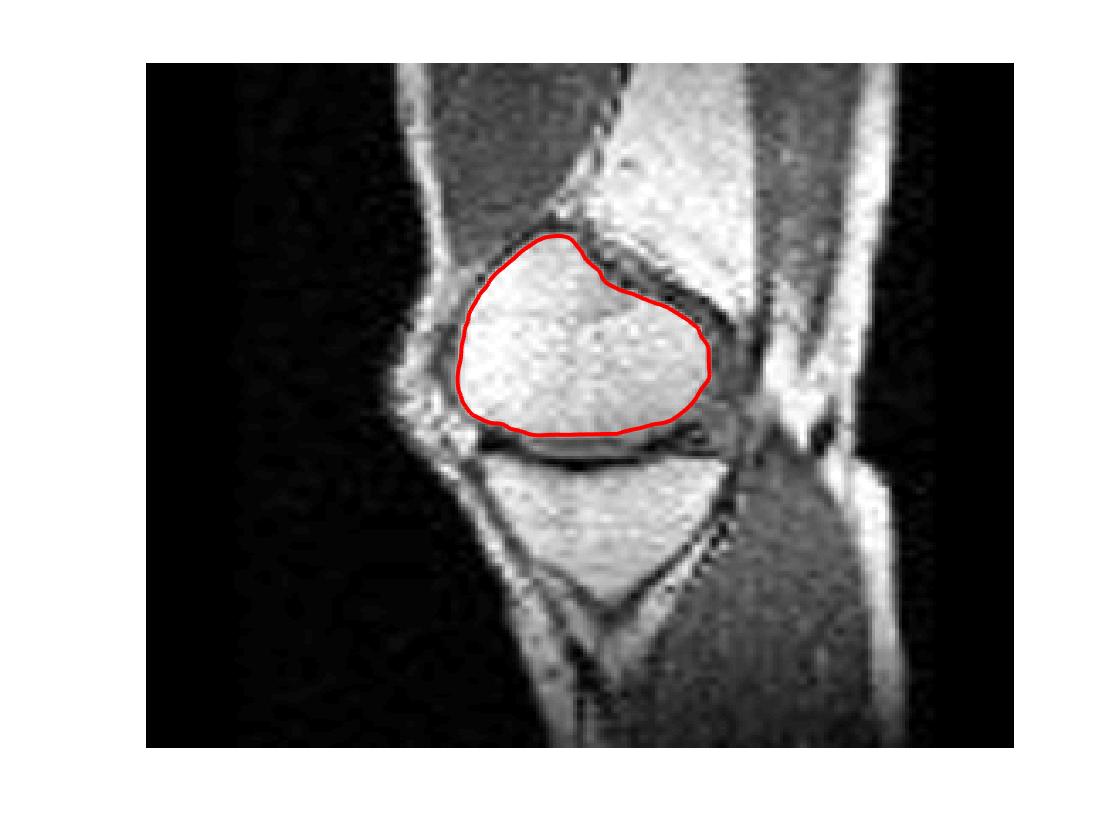

Four sets of test results are shown below. In Test 1 we compare models M1 – M6 to the proposed model M7 for two images which are hard to segment. The first is a CT scan from which we would like to segment the lower portion of the heart, the second is an MRI scan of a knee and we would like to segment the top of the Tibia. See Figure 9 for the test images and the marker sets used in the experiments. In Test 2 we will review the sensitivity of the proposed model to the main parameters. In Test 3 we will give several results achieved by the model using marker and anti-marker sets. In Test 4 we show the initialisation independence and marker independence of the Geodesic Model on real images.

In this test we give the segmentation results for models M1 – M7 for the two challenging test images shown in Figure 9. The marker and anti-marker sets used in the experiments are also shown in this figure. After extensive parameter tuning, the best final segmentation results for each of the models are shown in Figures 10 and 11. For M1 – M4 we obtain incorrect segmentations in both cases. In particular, the results of M2 and M4 are interesting as the former gives poor results for both images, and the latter gives a reasonable result for Test Image 1 and a poor result for Test Image 2. In the case of M2, the regularisation term includes the edge detector and the distance penalty term (see (4)). It is precisely this which permits the poor result in Figures 10(b) and 11(b) as the edge detector is zero along the contour and the fitting terms are satisfied there (both intensity and area constraints) – the distance term is not large enough to counteract the effect of these. In the case of M4, the distance term and edge detector are separated from the regulariser and are used to weight the Chan-Vese fitting terms (see (9)). The poor segmentation in Figure 11(b) is due to the Chan-Vese terms encouraging segmentation of bright objects (in this case), weighting enforces these terms at all edges in the image and near . In experiments, we find that M4 performs well when the object to segment is of approximately the highest or lowest intensity in the image, however when this is not the case, results tend to be poor. We see that, in both cases, models M5 and M6 give much improved results to M2 and M4 (obtained by incorporating the geodesic distance penalty into each). The proposed Geodesic Model M7 gives an accurate segmentation in both cases. It remains to compare M5, M6 and M7. We see that M5 is a non-convex model (and cannot be made convex [39]), therefore results are initialisation dependent. It also requires one more parameter than M6 and M7, and an accurate set to give a reasonable area constraint in (4). These limitations lead us to conclude M6 and M7 are better choices than M5. In the case of M6, it has the same number of parameters as M7 and gives good results. M6 can be viewed as the model M7 with weighted intensity fitting terms (compare (18) and (30)). Experimentally, we find that the same quality of segmentation result can be achieved with both models generally, however M6 is more parameter sensitive than M7. This can be seen in the parameter map in Figure 12 with M7 giving an accurate result for a wider range of parameters than M6. To show the improvement of M7 over previous models, we also give an image in Figure 13 which can be accurately segmented with M7 but the correct result is never achieved with M6 (or M3). Therefore we find that M7 outperforms all other models tested M1 – M6.

Test 2 – Test of M7’s sensitivity to changes in its main parameters. In this test we demonstrate that the proposed Geodesic Model is robust to changes in the main parameters. The main parameters in (20) are and . In all tests we set , which is simply a rescaling of the other parameters, and we set . In the first example, in Figure 12, we compare the TC value for various and values for segmentation of a bone in a knee scan. We see that the segmentation is very good for a larger range of and values. For the second example, in Figure 13, we show an image and marker set for which the Spencer-Chen model (M3) and modified Liu et al. model M6 cannot achieve the desired segmentation for any parameter range, but which can be attained for the Geodesic Model for a vast range of parameters. The final example, in Table 1, compares the TC values for various values with fixed parameters and . We use the images and ground truth as shown in Figures 12 and 13: on the synthetic circles image we obtain a perfect segmentation for all values of tested, and in the case of the knee segmentation the results are almost identical for any , above which the quality slowly deteriorates.